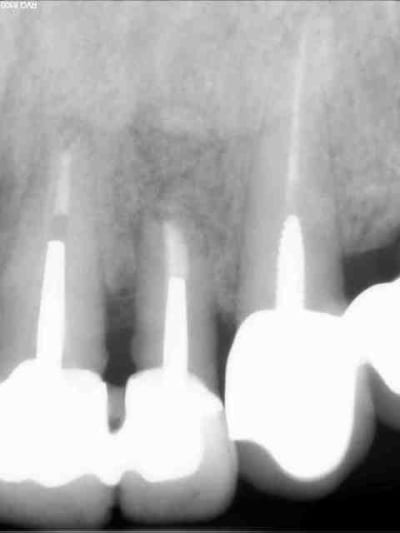

Pas trop nul à chier pour une fois :-)

Obturation a retro au MTA, beta TCP en comblement (plus de corticale osseuse vestibulaire). C'est un choix qui se discute, mais si certains ont des remarques constructives...je prend.